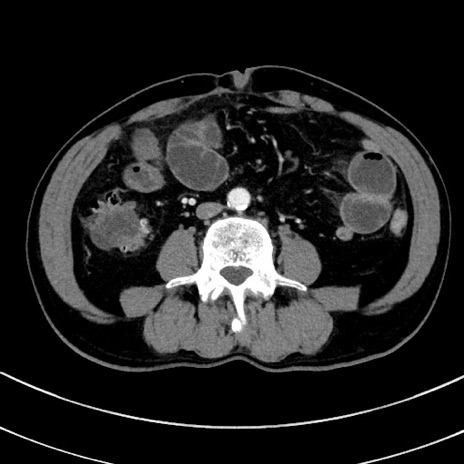

症例8(横断像)

【症例】 60歳代男性

【主訴】 黒色吐物

【現病歴】 4日前から嘔気自覚、2日前の朝食後にも嘔気あり、自分で手で嘔吐反射起こし嘔吐したところ血が混ざっていたため受診。

【既往歴】 5年前汎発性腹膜炎を伴う急性虫垂炎で手術、高血圧、前立腺肥大症、高脂血症

【身体所見】 腹部正中に手術癩痕あり 腹部平坦・軟圧痛なし膨満感あり

【データ】WBC 8400、CRP 4.54